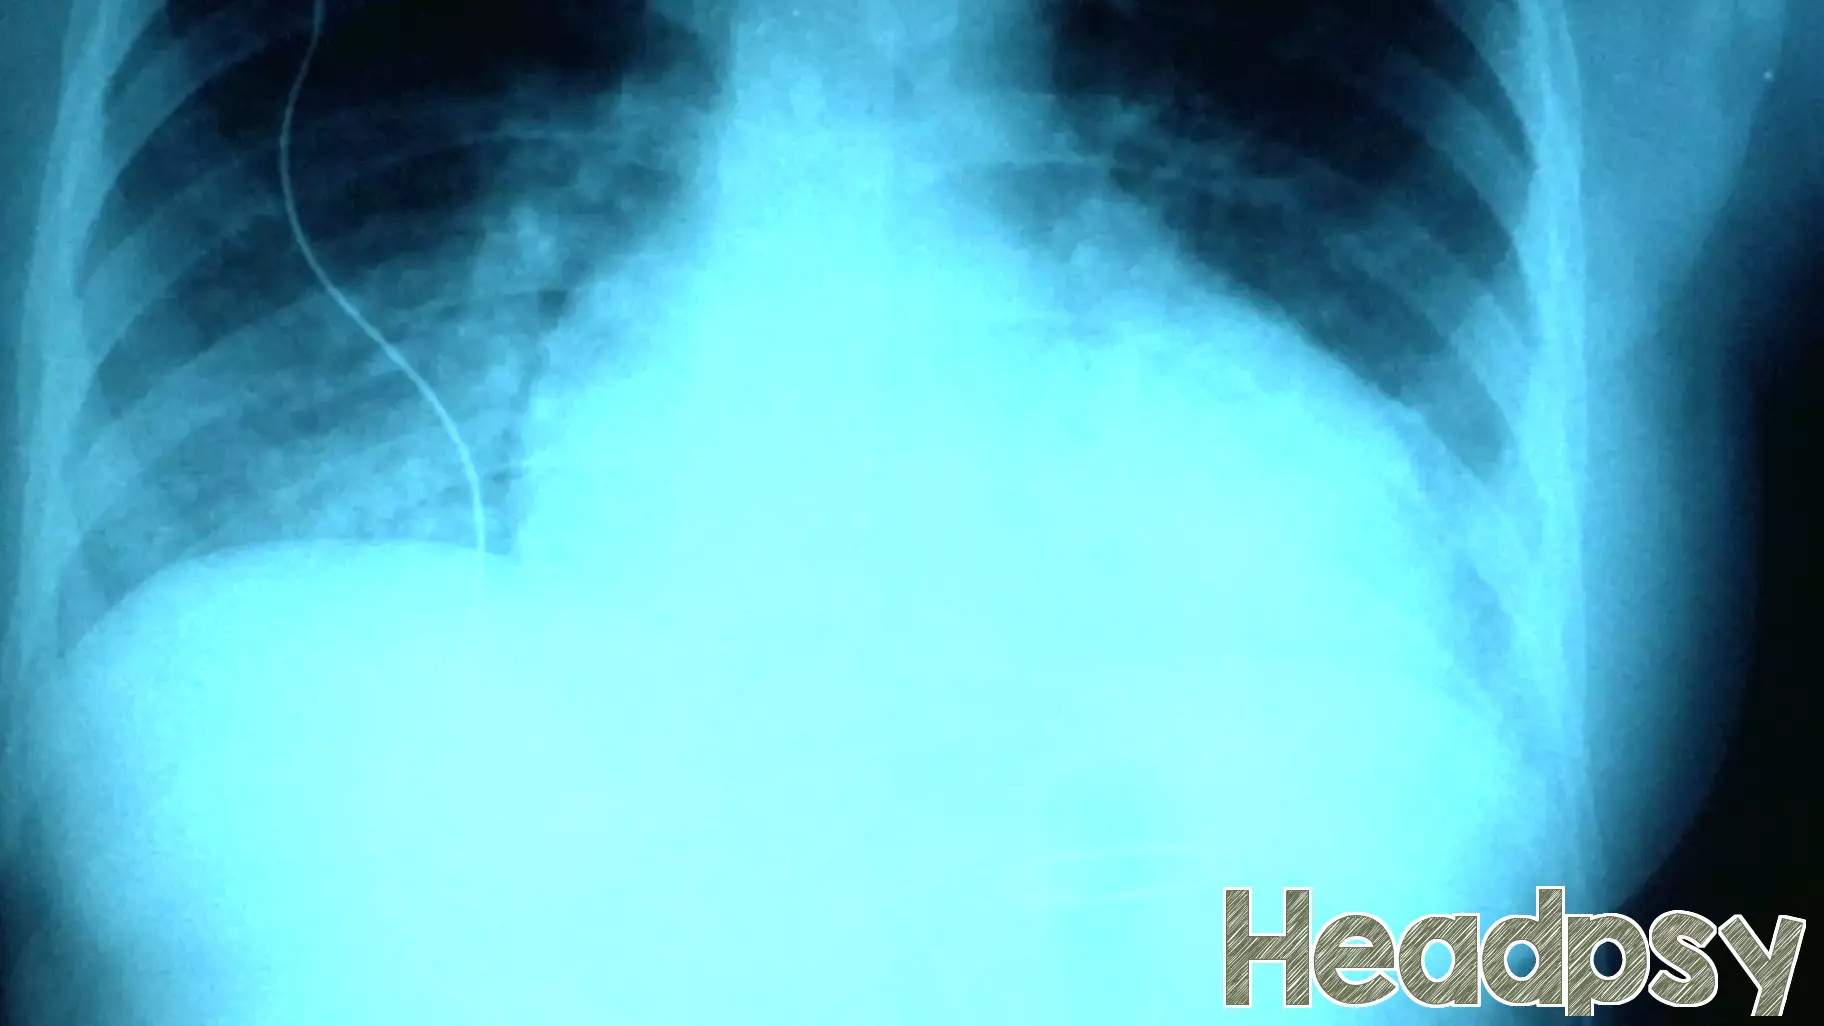

Recently, a family member encountered a challenging and anxiety-inducing situation when doctors discovered fluid in his lungs. The initial concern was that this fluid could be indicative of cancer, leading to a whirlwind of emotions for our family. As we navigated through the uncertainty, fear loomed large, overshadowing our daily lives.

The prospect of cancer is terrifying, and the waiting period for definitive answers can feel like an eternity. However, as the medical team conducted further tests, a surprising twist emerged. The diagnosis shifted away from cancer, revealing that the fluid was related to heart failure instead. While heart failure is serious, the relief that it was not cancerous was palpable.

This experience highlighted the importance of support and communication during medical crises. It reminded us that sometimes, what initially appears to be devastating news can lead to a hopeful outcome. We are now focused on managing the heart condition, grateful for the clarity that has emerged from such a stressful time.